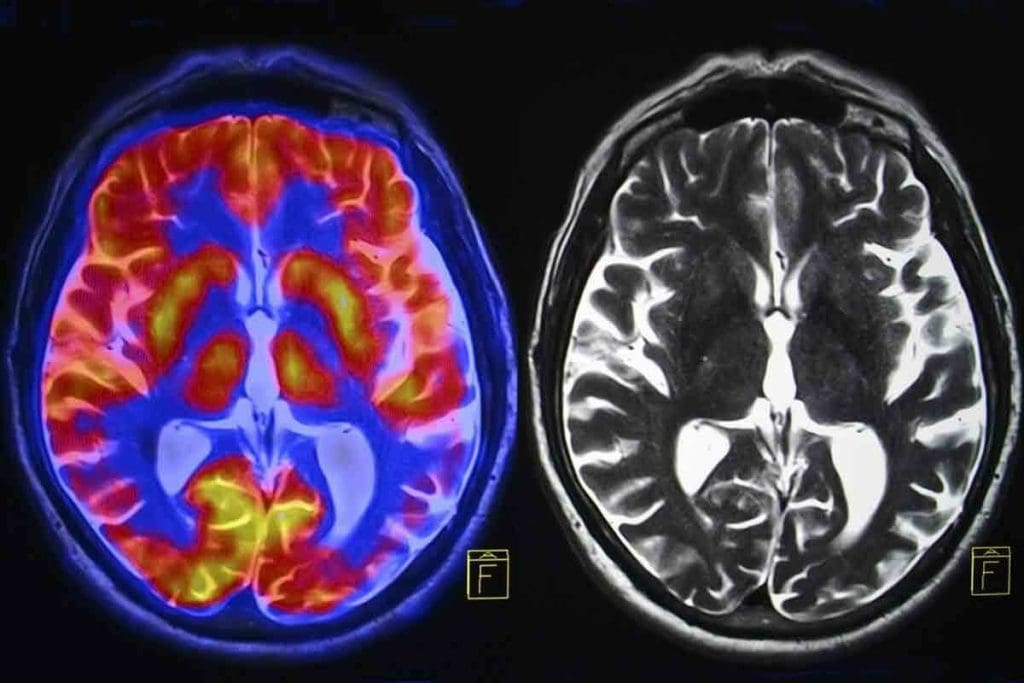

We are seeing a big change in how we diagnose brain tumors with new CT methods. These advanced techniques help us better understand and manage brain tumors.

CT Perfusion Imaging Applications

CT perfusion imaging is a key tool for brain tumor evaluation. It shows us how tumors grow and how well they block blood flow. A study in Nature found it can tell the difference between a tumor coming back and damage from treatment.

Key applications of CT perfusion imaging include:

- Assessing tumor angiogenesis

- Evaluating blood-brain barrier disruption

- Monitoring treatment response

Dual-Energy CT and Material Decomposition

Dual-energy CT lets us break down materials, which helps in understanding tumor makeup. It scans at two energy levels to spot different materials by their atomic numbers.

Experts say, “Dual-energy CT can spot important tumor features like calcifications or hemorrhage, key for diagnosis.”